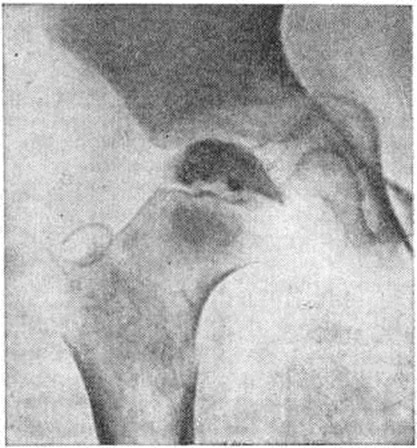

Пертеса болезньПертеса болезнь (G. G. Perthes, немецкий хирург, 1869—1927; синонимы болезнь Легга — Кальве — Пертеса) — асептический некроз головки бедренной кости. Впервые описана Г. Пертесом в 1910 год Пертеса болезнь относится к группе остеохондропатий (смотри полный свод знаний). Составляет 1—3% среди заболеваний опорно-двигательного аппарата у детей. В возрасте до 5 лет встречается редко, наиболее поражаемый возраст 6—10 лет. Мальчики болеют в 4—5 раз чаще. Заболевание обычно носит односторонний характер. Этиология остаётся неясной. Существуют различные взгляды на причину асептического некроза головки бедренной кости (перенесённая инфекция, нарушения обмена, эндокринные расстройства, аномалия развития сосудов, травма). Непосредственной причиной асептического некроза головки бедра следует считать нарушение местного кровообращения, в котором определённую роль может играть травма. Клиническая картина. Первые клинические, симптомы заболевания нехарактерны, непостоянны, слабо выражены. Появляется хромота, которая быстро исчезает при разгрузке конечности, но затем вновь возобновляется. Умеренные боли в области поражённого тазобедренного сустава нередко иррадиируют в коленный сустав. Боли обычно возникают днём, во время ходьбы. Клинические, исследование выявляет незначительную атрофию мягких тканей бедра и голени, небольшую сгибательную контрактуру тазобедренного сустава, ограничение отведения и внутренней ротации бедра. Пальпация тазобедренного сустава слегка болезненна. G разгрузкой сустава (постельный режим) указанные жалобы быстро исчезают. Симптом Александрова (смотри полный свод знаний Туберкулёз внелёгочный, туберкулёз костей и суставов) слабо положительный или отсутствует. Длина конечности, как правило, не изменена, но может наблюдаться небольшое укорочение или удлинение её в связи с угнетением или раздражением росткового хряща. Симптом Тренделенбурга (смотри полный свод знаний Тазобедренный сустав) в большинстве случаев положительный. Общее состояние ребёнка не страдает. Температура не повышена, кровь в норме. Диагностика. В связи с отсутствием характерных клинические, признаков Пертеса болезнь часто диагностируют с опозданием. Решающую роль в диагностике играет рентгенологическое исследование, при этом обязательна рентгенография обоих тазобедренных суставов в прямой проекции и в положении Лауэнштейна (смотри полный свод знаний Тазобедренный сустав). Пертеса болезнь характеризуется определённой последовательностью морфологический изменений, происходящих в головке бедренной кости, что рентгенологически выражается 5 стадиями процесса (С. А. Рейнберг). В первой стадии (стадия подхрящевого некроза) отмечают остеопороз головки и шейки бедра, расширение суставной щели. Головка теряет сферическую форму, под куполом её появляется узкая полоска просветления, что свидетельствует о начальных стадиях сплющивания. Все эти изменения более отчётливо видны на рентгенограмме тазобедренного сустава в положении Лауэн. Вторая стадия — стадия импрессионного перелома: головка бедренной кости уплощена, уплотнена, лишена структурного рисунка, имеет неровные извилистые контуры (рисунок 1). Третья стадия, наиболее характерная для Пертеса болезнь,— стадия с образованием секвестроподобных теней. Некротические массы расщепляются и постепенно рассасываются. Сохранившиеся островки гомогенного некроза, окружённые вновь образованной соединительной тканью и хрящом, напоминают секвестры (рисунок 2, а). Если ребёнок продолжает пользоваться конечностью, головка бедра ещё больше уплощается, суставная щель становится шире, чем во второй стадии. Щель эпифизарного хряща расширяется, приобретает извилистые рыхлые контуры. Шейка утолщается и укорачивается в результате нарушения процессов энхондрального роста. В тяжёлых случаях в субхондральных её отделах выявляются очаги разрежения. Соответственно деформации головки бедра изменяется и форма вертлужной впадины, её крыши. Проксимальный конец бедра может быть смещён в положение небольшого подвывиха кнаружи и кверху. Четвертая стадия — стадия восстановления структуры (рисунок 2, б). Секвестроподобные тени не определяются, но структура головки долгое время остаётся неравномерной, постепенно приобретая нормальный губчатый рисунок. Деформация головки сохраняется на всю жизнь. Чётких рентгенологических границ между описанными четырьмя стадиями не существует. |